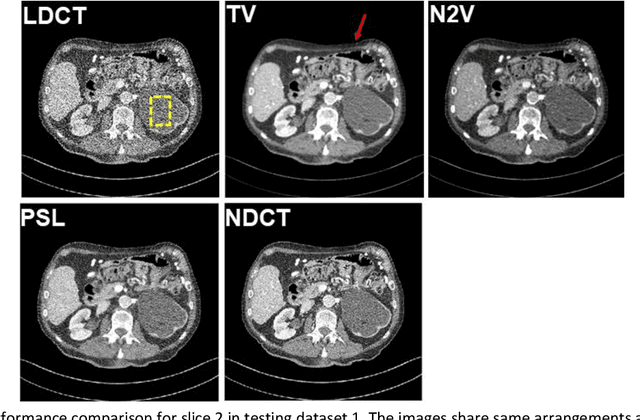

Abstract:Despite the indispensable role of X-ray computed tomography (CT) in diagnostic medicine field, the associated ionizing radiation is still a major concern considering that it may cause genetic and cancerous diseases. Decreasing the exposure can reduce the dose and hence the radiation-related risk, but will also induce higher quantum noise. Supervised deep learning can be used to train a neural network to denoise the low-dose CT (LDCT). However, its success requires massive pixel-wise paired LDCT and normal-dose CT (NDCT) images, which are rarely available in real practice. To alleviate this problem, in this paper, a shift-invariant property based neural network was devised to learn the inherent pixel correlations and also the noise distribution by only using the LDCT images, shaping into our probabilistic self-learning framework. Experimental results demonstrated that the proposed method outperformed the competitors, producing an enhanced LDCT image that has similar image style as the routine NDCT which is highly-preferable in clinic practice.